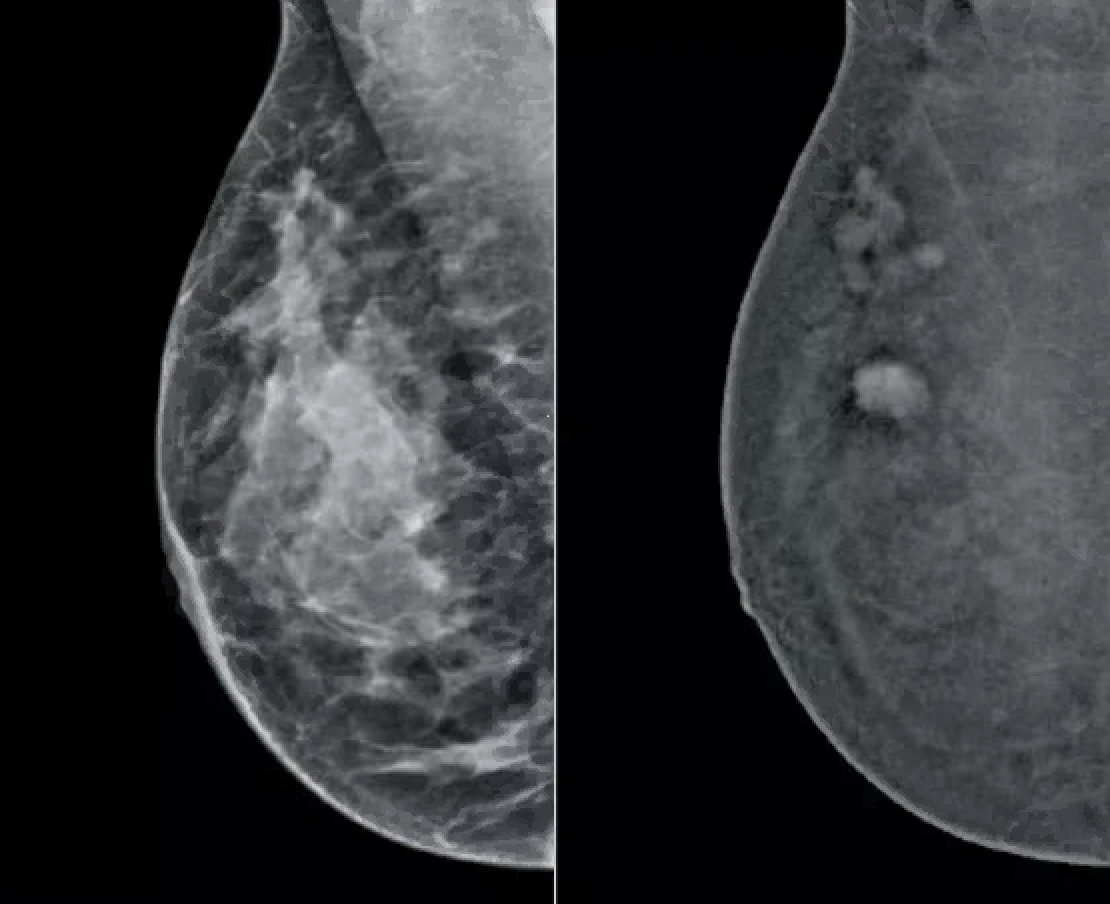

Afbeelding via Tromp/Hologic website: voorbeeld mammografie zonder en met contrast.

Bij CEM worden röntgenopnames van de borst(en) gemaakt nadat via een infuus jodiumhoudend contrastmiddel is toegediend. Door het gebruik van contrast wordt borstkanker beter zichtbaar en kan de aanwezigheid van een tumor soms ook beter worden uitgesloten. De diagnostische resultaten zijn vergelijkbaar met die van een MRI-scan, terwijl CEM sneller is en minder belastend voor de patiënt. Daarnaast laten studies zien dat na toepassing van CEM vaak minder aanvullende onderzoeken nodig zijn, wat ook kan bijdragen aan lagere zorgkosten.